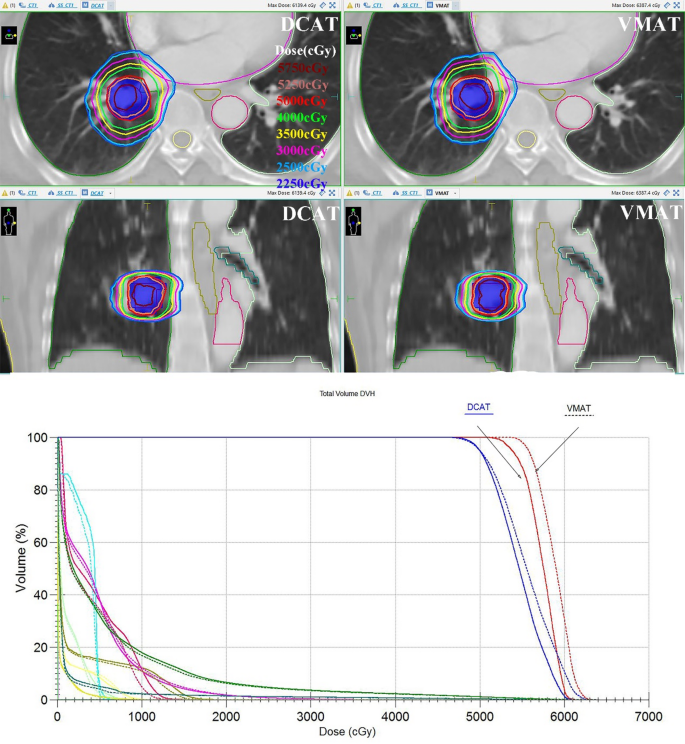

Table 1 summarizes the statistical analyses of the dosimetric parameters of the 2-group plans for targets (mainly the PTV), and Fig. 1 compares selected target parameters for the 2-group plans. When normalizing all plans to 100% of the prescribed dose covering 95% of the PTV, they all met the dose limits described in the RTOG 0813 protocol. The DCAT group had more considerable high and intermediate dose spillage than the VMAT group, as evidenced by a more significant CI (1.15 vs. 1.13, P < 0.05) than the VMAT group and greater D2cm (52.18 Gy vs. 50.68 Gy, P < 0.001) and R50% (4.86 vs. 4.52, P < 0.001) than the VMAT group but judging from the absolute values, the differences in CI, D2cm, and R50% between the 2-group plans were not that big (exceeding 1.74%, 2.87%, and 6.70%, respectively). The dose homogeneity in PTV was better in the DCAT group, as evidenced by the fact that the HI (1.24 vs. 1.13, P < 0.05) and D2% (62.60 Gy vs. 69.07 Gy, P = 0.001) of the PTV were smaller than those of the corresponding VMAT group, and the D98% (44.54 Gy vs. 43.10 Gy, P < 0.05) of the PTV was bigger than that of the VMAT group. Figure 2 shows the transverse and coronal dose distributions, as well as the DVH for the DCAT plan and the VMAT plan in one case, and the DCAT plan had a more uniform target dose (less volume of 5750 cGy, comparable volume of prescription dose) and comparable OARs dose compared to the VMAT plan.

Comparison of DCAT and VMAT plans for a typical patient. The upper and middle panels show isodose distributions for the DCAT (left) and VMAT (right) plans. Comparable isodose distributions were obtained with the DCAT plan. The OARs include ipsilateral lung, contralateral lung, spinal cord, ipsilateral PBT, esophagus, heart, great vessels, ipsilateral brachial plexus, and skin. The lower panel shows the DVH comparison for both plans. The solid line represents the DCAT plan, and the dashed line shows the VMAT plan (red, ITV; blue, PTV; green, ipsilateral lung; yellow, spinal cord; cyan, ipsilateral PBT; pink, heart; carmine, great vessels; other OARs not shown). DCAT plan had a more uniform target dose and comparable OAR dose to the VMAT plan. Abbreviations: ITV internal target volume, PTV planning target volume, PBT proximal bronchial tree, DCAT dynamic conformal arc therapy, VMAT volumetric-modulated arc therapy, DVH dose volume histogram.